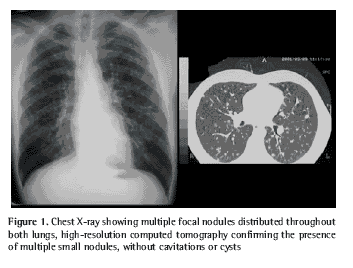

The chest X-ray showed multiple focal nodules in both lungs. High-resolution computed tomography confirmed the presence of these small nodules, the largest of which measured 10 mm in diameter. The lesions were located predominantly in the upper lobes and, to a lesser extent, throughout the medial pulmonary fields, sparing the bases and the costophrenic angles. There were no cysts or cavitations within these small nodules. No enlarged lymph nodes were detected (Figure 1).

The high-resolution computed tomography findings most frequently described are pulmonary nodules with cystic alterations distributed between the central and peripheral portions, usually sparing the lung bases. The lesions evolve from firm nodules to cavitations, to cysts with thick walls and finally to cysts with thin walls. Some lesions might regress, but, upon reaching the cystic form, they tend to remain stable or increase in size. This progression is generally parallel to the deterioration of the pulmonary function(21).

No cystic lesions were detected in the X-rays of this patient, probably due to the short time elapsed between the onset of the symptoms and the diagnosis. That might also explain the marked resolution of the lesions following smoking cessation(10).